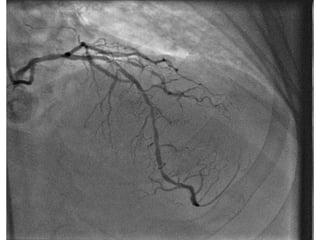

A 49-year-old male presented with syncope and was found to have cardiomyopathy with severely reduced ejection fraction less than 25% based on echocardiogram findings. Cardiac catheterization showed severe blockages of the left anterior descending and circumflex arteries. Despite a non-ischemic etiology, the patient was evaluated for an implantable cardioverter-defibrillator due to the reduced ejection fraction. A separate 33-year-old male presented with chest pain and was diagnosed with an anterior STEMI based on ECG findings.